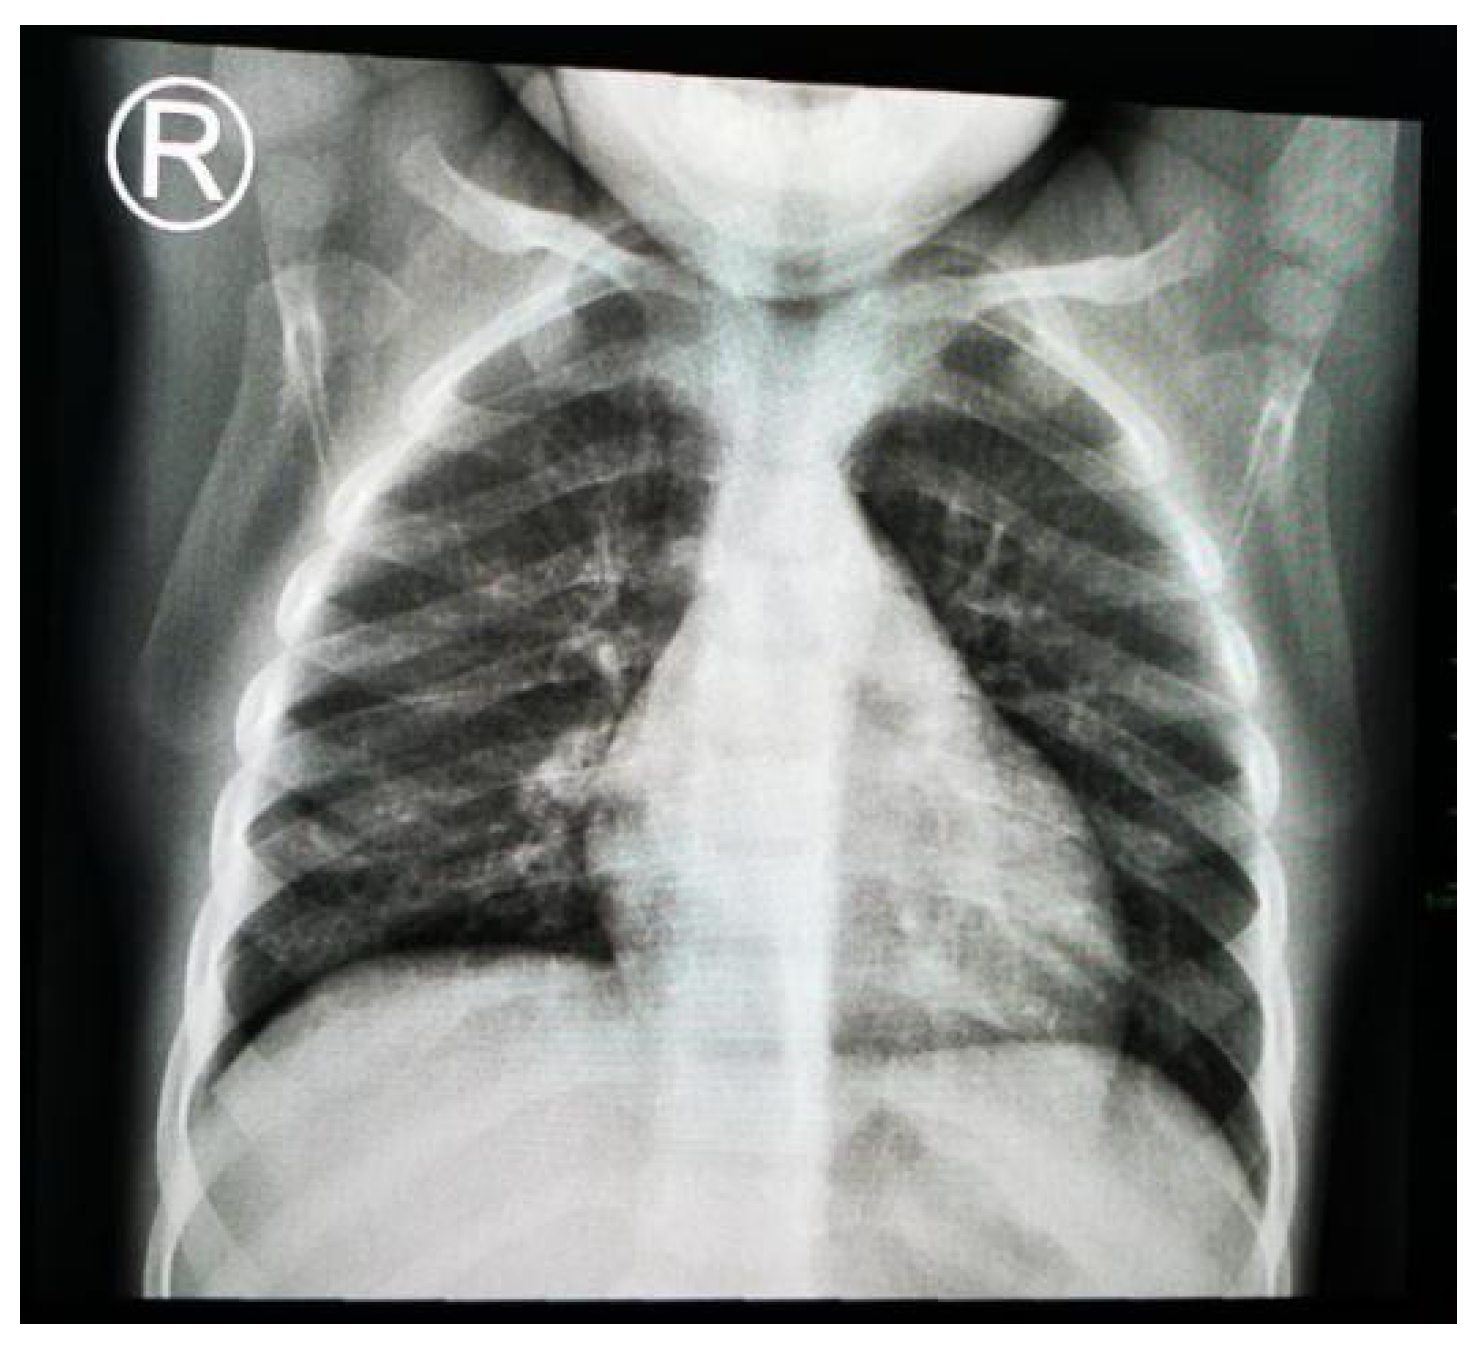

1.9.1. Case 1

1.9.2. Case 2